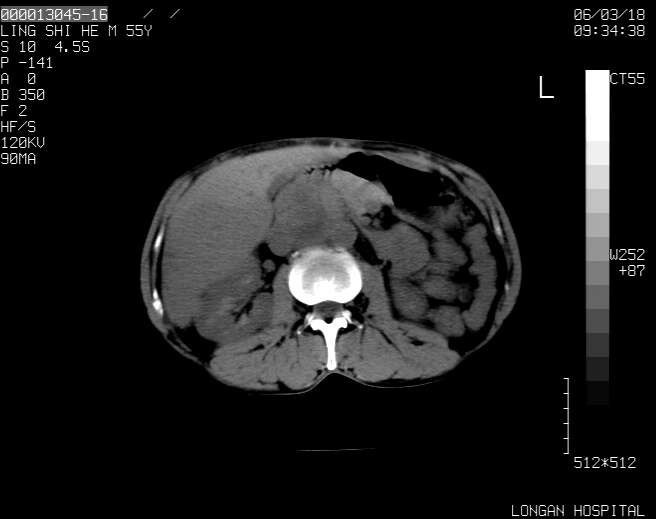

以下是引用guzhongliangddd在2006-3-21 22:13:00的发言:[br]病灶主要位于肝右叶的后份,内见异常血管,门脉主干及右支受侵{提示有癌栓形成},门腔间隙内见增大淋巴结。肝左叶内未见异常。

以下是引用zhuxinli在2006-3-22 1:23:00的发言:[br][br] 病灶主要位于肝右叶的后份,内见异常血管 .门脉右支截断,右叶前段早期强化(考虑动静脉漏),腹膜后肿大淋巴结,病灶逐渐强化,考虑为胆管细胞癌[br]